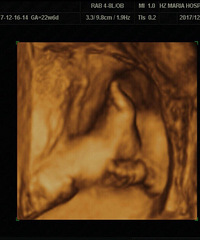

买了根高档验孕棒一测就准

怎么说呢,TA就这么来了从10月开始就处于备用状态因为本身大姨妈就不太正常,自己又比较马虎,过一个星期就会用验孕棒检查一下我们婚期是11月25日,22号准备回家结婚那天检查了一下还是一道杠。想想自己应该就是没怀上,就大大咧咧的回家结婚了。折腾了几天,26号回了嘉兴。27号想